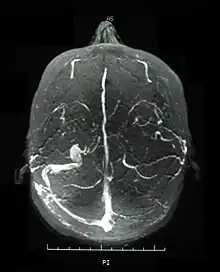

Central nervous system (CNS) involvement most often occurs as a chronic meningoencephalitis. Lesions tend to occur in the brainstem, the basal ganglia and deep hemispheric white matter and may resemble those of multiple sclerosis (MS). Brainstem atrophy is seen in chronic cases.

Neurological involvements range from aseptic meningitis to vascular thrombosis such as dural sinus thrombosis and organic brain syndrome manifesting with confusion, seizures, and memory loss. Sudden hearing loss (sensorineural) is often associated with it.[4] They often appear late in the progression of the disease but are associated with a poor prognosis.